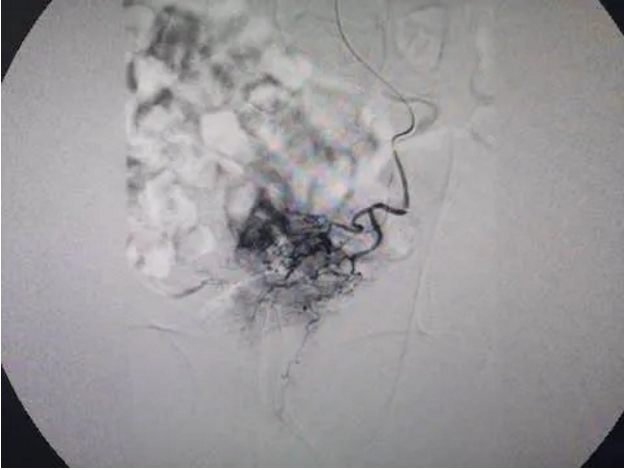

例如,一位54岁男性患者,因肾结石经皮肾镜取石术后出血,临床危急值,经急诊介入行肾动脉造影发现肾出血伴动静脉瘘形成,经栓塞出血动脉后不仅止血,同时封闭动静脉。据悉,一批出血涵盖胸部、泌尿、消化、生殖系统病变出血患者,通过红河州第三人民医院放射影像科介入治疗后均成功止血,如是肿瘤伴出血患者,同时还可以兼顾对肿瘤病变治疗。

主动脉夹层病变2例均成功治疗;肝癌患者、伴或不伴门静脉癌栓,无外科手术指征者,均成功治疗延长患者生存期、提高生活质量,部分肝内多发肝癌患者,无外科手术指征,均成功治疗且明显延长了生存期,部分患者均控制良好,现定期随访复查中;完成1例布加氏综合征患者,患者因下腔静脉肝段阻塞伴侧支血管扩张纡曲,双下肢浅静脉曲张伴皮下瘀斑,色素沉着,经介入开通闭塞下腔静脉后症状立即改善,现随访中;下腔静脉滤器置入在下肢深静脉血栓形成溶栓治疗中预防肺栓塞发生的应用,已完成多例;肝血管瘤经股动脉入路硬化栓塞治疗已完成数十例,以往传统外科手术切除,创伤大,恢复慢,现采用介入手段治疗后,创伤小,并发症少,恢复快,疗效肯定,在合并动-门静脉分流时,可同时行分流道封堵治疗;全身各部分血管畸形介入治疗已完成多例,包括软组织血管瘤、动静脉分流、静脉畸形等;肝脓肿经皮穿刺引流术,经积极对症处理,恢复快,疗效好;子宫肌瘤及子宫腺肌症介入治疗已完成多例,保证了身体器管的完整性,真的做到“原装生活”;配合产科完成凶险性前置胎盘双侧髂内动脉临时球囊阻断术一例,保证了母子安全,减少了致命性大出血风险;非血管介入治疗包括气管或主支气管狭窄气道支架置入完成数例、食道癌狭窄行支架置入术多例、胆道恶性梗阻行经皮肝穿刺内外引流术及支架置入术多例;还有空肠营养管置入、下肢静脉曲张泡沫硬化治疗等等……

又如,栓塞治疗——出血的栓塞:晚期肿瘤常引发大出血,如不及时控制,常引起其它并发症,导致死亡。如肺癌、膀胱癌、胃底食管静脉曲张破裂等,该类患者应行急诊介入治疗,栓塞其供血血管,控制出血。如支气管动脉、髂内动脉、胃冠状静脉等。肿瘤的栓塞:肝癌、肺癌、盆腔等部位肿瘤均可通过导管将栓塞剂注入供血动脉,阻断其血运,达到“饿死肿瘤”的目的。